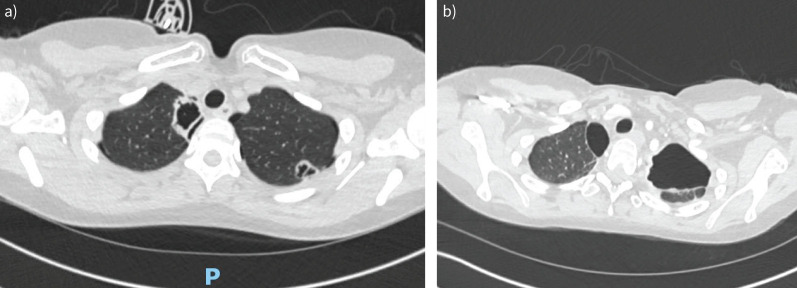

One of the respiratory complications of rheumatoid arthritis (RA) is formation of lung nodules, which can rupture to cause pneumothoraces. We present a case of recurrent pneumothoraces due to accelerated RA nodulosis, secondary to biologic therapy. https://bit.ly/3WBhgOe.

Abstract Image